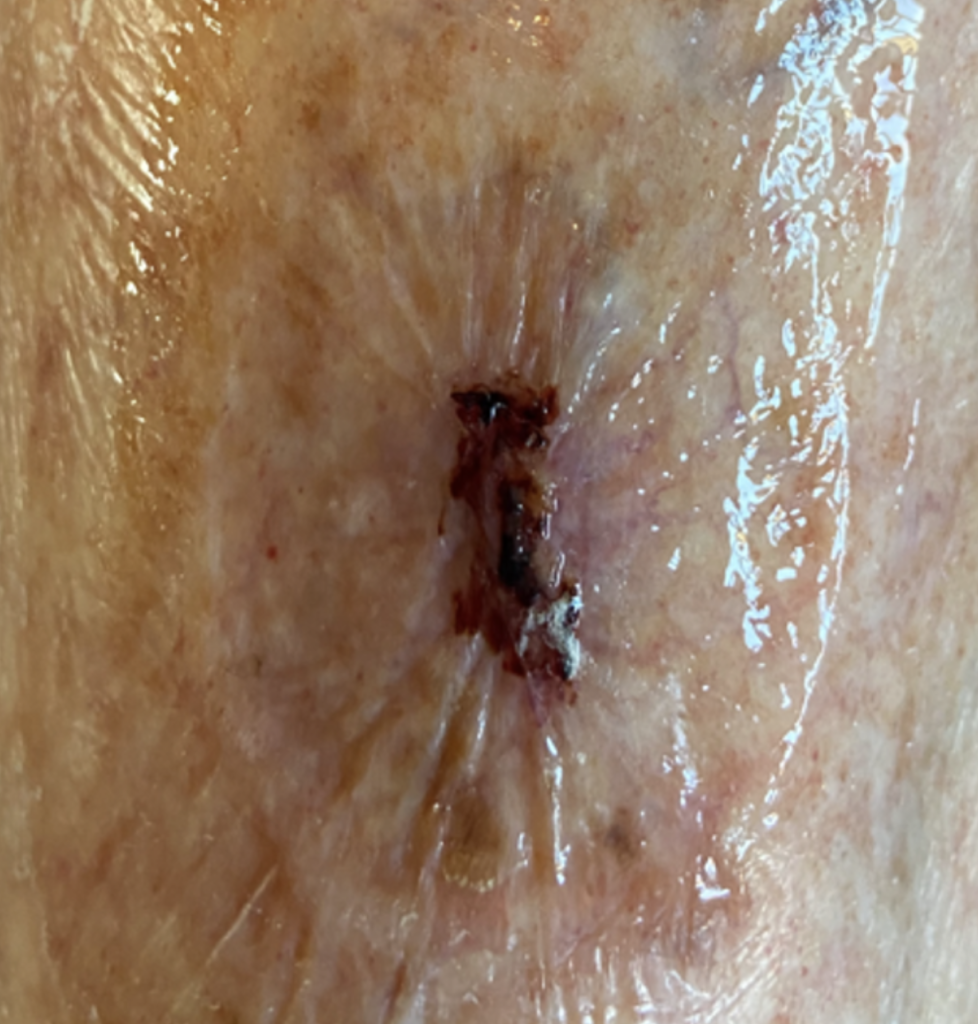

In the first 24 hours after EVLA and sclerotherapy, the patient reported mild pain, tightness, heaviness along the ablation tract, and a dull ache in the medial calf. Despite these symptoms, pain relief requirements were minimal; only two paracetamol tablets were taken on the evening of the procedure, with no need for further analgesia overnight. The patient adhered to the post procedural instructions regarding compression, wearing full length compression hosiery continuously. Tolerance of the hosiery was reported as good; however, it was observed that an initial adjustment period was required to become accustomed to the silicone welt, which is designed to prevent garment slippage. On the morning following the intervention, minor bleeding was noted at the catheter insertion site (Fig.11).

Accordingly, the hosiery was rolled down to remove the small dressing. As no further bleeding was observed, reapplication of the dressing was deemed unnecessary, and the hosiery was promptly repositioned.